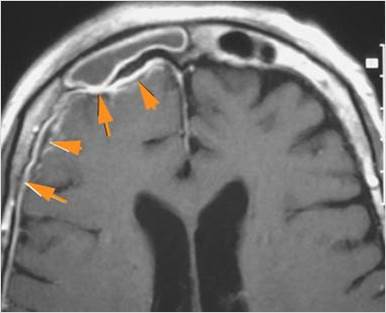

There is evidence of thrombus, thrombophlebitis or other occlusive or inflammatory process of the cortical veins, sphenoparietal sinus or sagittal sinus. [Yes/No]